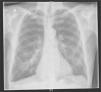

Patient 1A 71 year old male presented to the emergency department with a history of chest pain and shortness of breath. A chest X-ray (Fig. 1) showed a recurrent right hydropneumothorax, this was because in the previous two months, the patient had had two previous episodes of right pneumothorax which had been managed successfully by a right tube thoracostomy. He had no significant medical history. He was an ex-smoker with a 40 pack-year history. He also reported a heavy asbestos exposure in the past.

With the third episode, he was referred for surgical intervention while he still had the right-side tube thoracostomy in place. No chest CT-scan was performed.